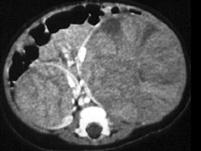

问题 男,2岁,触及腹部包块,未及肿大淋巴结,请根据所示图像,选择最可能诊断 ( )

选项 A、双侧肾癌 B、双肾神经母细胞瘤 C、双肾转移瘤 D、双侧肾母细胞瘤(Wilms瘤) E、双肾淋巴瘤

答案 D